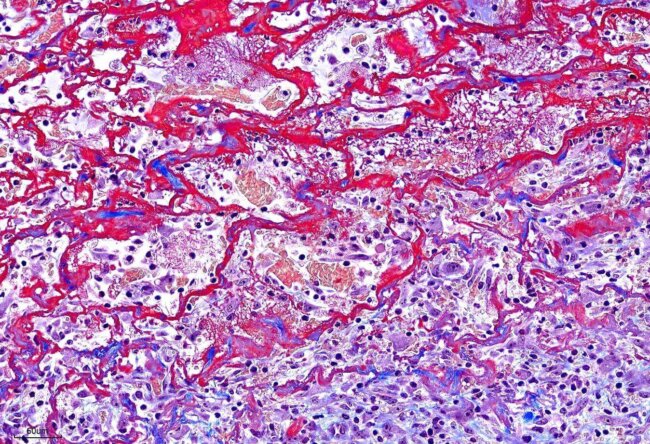

血管壁周圍細胞瘤(Perivascular wall tumor, PWT)

皮膚傷口的Masson Trichrome染色